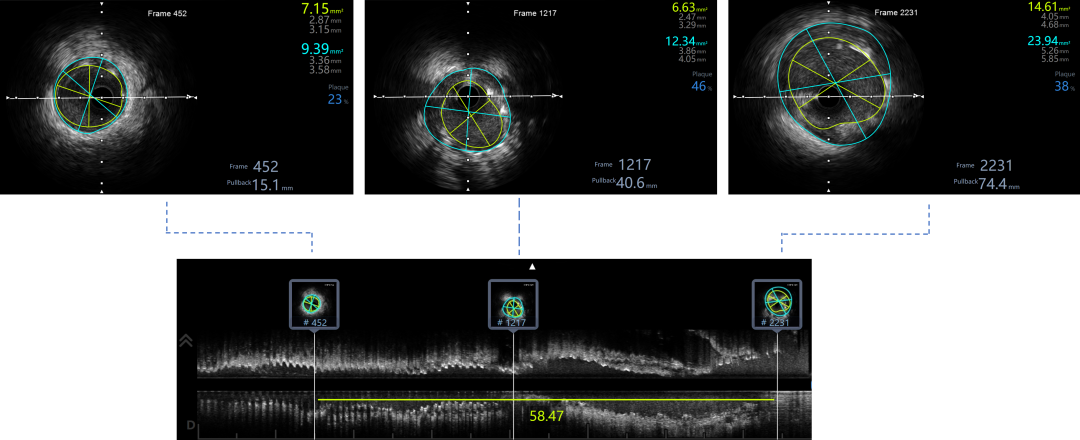

Ballon 2.0*15mm Dilatation & IVUS check

NC Ballon & IVUS check

IVUS提示LAD近中段弥漫钙化,接近270度,钙化长度约26mm

IVUS LCX-LM,RUN2

支架膨胀、贴壁良好,LCX开口MSA 5.68mm²,LM MLA 5.67mm²。

IVUS LAD-LM,RUN3,LAD口部MSA 9.03mm²,LM MSA 10.18mm²